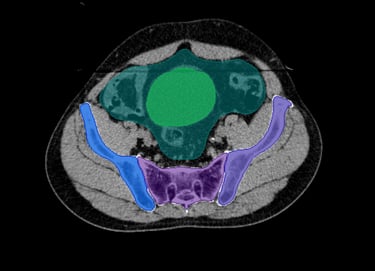

O SegmentaR foca na segmentação automática das três regiões fundamentais para o planejamento de radioterapia: cabeça e pescoço, tórax e pelve. Essas são as regiões essenciais que todo profissional precisa para uma segmentação precisa e eficiente.

Pelve

Bexiga

Bulbo Peniano

Cauda Equina

Sacro

Fêmur Esquerdo

Fêmur Direito

Bolsa Intestinal

Reto

Ilíaco Direito

Ilíaco Esquerdo

Sínfise Púbica

Rim Esquerdo

Rim Direito